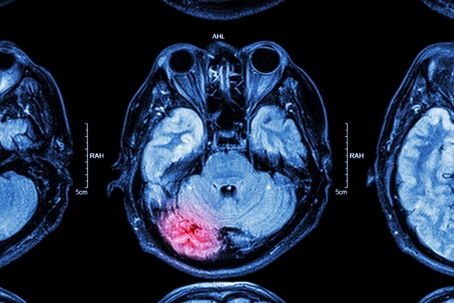

Understanding Traumatic Brain Injuries (TBIs) from Car Accidents

Traumatic Brain Injuries (TBIs) are a significant concern in the aftermath of car accidents. A TBI occurs when an external force causes the brain to dysfunction, often resulting from a violent blow or jolt to the head. In the context of vehicular accidents, TBIs can range from mild concussions to severe brain damage, leading to long-term cognitive and physical impairments.